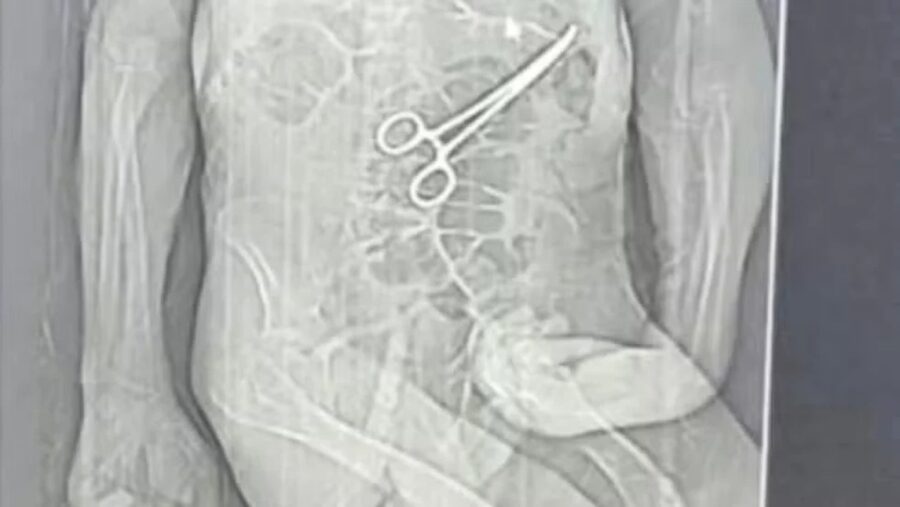

Um homem de 68 anos morreu na véspera de Natal, após passar por duas cirurgias no Hospital Municipal de João Pinheiro, no noroeste de Minas Gerais. A família de Manoel Cardoso de Brito acusa a unidade de erro médico, alegando que uma pinça cirúrgica teria sido deixada dentro do corpo do paciente após o primeiro procedimento.

A Secretaria Municipal de Saúde confirmou que um corpo estranho foi retirado durante a cirurgia e informou que uma sindicância foi aberta para apurar o caso.